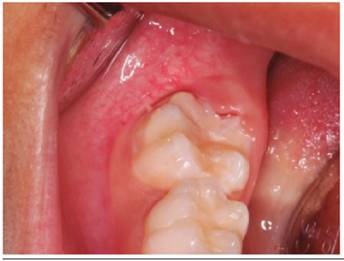

Luego de considerar las medidas de bioseguridad se procedió con el tratamiento de la pieza 46 (Figura 1), se realiza aislamiento relativo por la falta de erupción total de la pieza y la excesiva sensibilidad del paciente, aplicó brix 3000 (gel enzimático para la remoción a traumática de tejido infectado) (brix SRL Argentina), sobre las superficies infectadas de la pieza 46, luego de 2 minutos, con una cureta de dentina (Mayleffer N° 46) eliminamos estructura dental con HIM (Figura 2), se lavó con agua, y secó, se realizó desproteinización de la cavidad dentaria con una bolita de algodón embebida con hipoclorito de sodio al 5% por 30 segundos, y se enjuagó con una bolita de algodón embebida en agua, secado con bolitas de algodón (Figura 3), luego de cambiar el aislamiento relativo; se aplicó el adhesivo de 7ma generación Palfique Bond (Tokuyama), por la sensibilidad del paciente, se airea, fotocura por 20 segundos (Figura 4), y se aplica Giómero fluido F00 de reconstrucción (Beautifil Flow Plus de Shofu inc.), dando forma con el bruñidor para resina cabeza de huevo y se fotocuró por 20 segundos (Figura 5). Se utilizó el Giómero fluido F03 de sellado de fosas y fisuras (Beautifil Flow Plus de Shofu inc.) fotocurando por 20 segundos (Figura 6). Finalmente se comprueba el ajuste oclusal con una fresa cilíndrica plana (108-009) eliminando excesos y porosidades (Figura 7a).